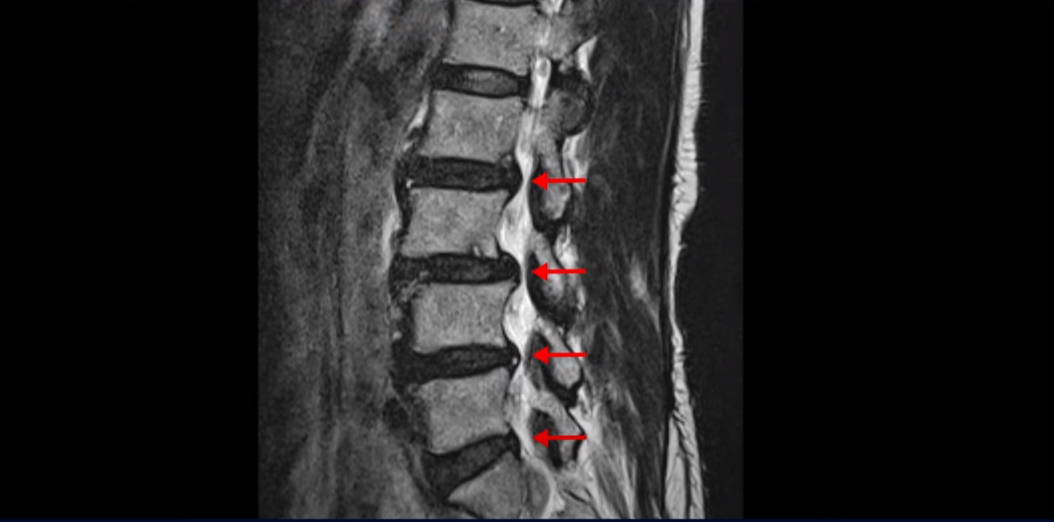

이 환자분은 1년 전에 협착증과 전방전위증으로 2주 동안 입원하고 치료가 끝난 분입니다. 1년 후인 최근에 허리가 아닌 무릎 문제로 병원에 오셨다가 흔쾌히 이 치료후기 영상을 찍어주셨습니다. 치료가 끝난 지 1년이 지났는데 허리 문제 없이 건강하게 잘 지내고 계실까요? 제가 이분 MRI를 보면서 왜 이런 갑자기 발병한 협착증 환자분일수록 치료가 더 쉽고 빠른지, 왜 신경이 눌렸다는데도 수술을 안 해도 되는지, 또 치료는 어떻게 하는지 자세히 설명 드리겠습니다.

이분 허리를 보면 여러 마디의 퇴행성 디스크와 협착이 있습니다.

2번 3번과 3번 4번은 신경다발이 지나가는 척추관도 좁아져 있습니다.

또 3번 4번에는 척추뼈가 밀려나간 전방전위증도 있습니다.

이분은 정형외과 병원에서 3마디 디스크 파열이라고 수술 권유를 받았는데 저희는 디스크 파열은 잘못된 진단이라고 봅니다. 여러 마디 보이는 디스크 문제는 파열이 아닌 퇴행성디스크들이고 아픈 원인은 전방전위와 협착증 증상입니다. 전방전위와 협착증이긴 하지만 아주 심한 게 아니고 발병한지도 얼마 되지 않아서 근육재활치료를 하면 2주 정도면 빨리 호전될 수 있는 상태였습니다. 왜 이런 환자가 치료하기 훨씬 쉬운 건지, 치료는 어떻게 하는 건지 지금부터 설명 드립니다.

이분이 처음 발병한 건 저희 치료를 시작하기 불과 2주 전입니다. 만일 이분이 아프기 전인 몇 달 전에 MRI를 찍었다면 지금 보시는 MRI와 많이 다를까요? 정답은 전혀 차이가 없다입니다. 뼈가 밀려나가고 신경 구멍이 좁아진 건 이미 오래 전에 벌어진 일입니다. 뼈가 밀려나가고 신경 구멍이 좁아져 있는 채로 아무런 증상을 느끼지 않고 66세까지 잘 산 것입니다. 이런 걸 잠복 협착이라고 합니다. MRI로 협착이 보이지만 아무런 증상이 없다는 뜻입니다.